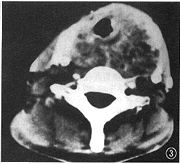

图3 气管ACC,后部为主,绕两侧生长,气管腔形态不规则,黏膜面光整,肿瘤呈筛样改变,将甲状腺向两侧推移并累及之

5.气管ACC的特殊表现:33例ACC中,以发生在气管的表现最具特征,肿瘤绕着气管向腔外深部生长,后部为主,管腔受压变形而黏膜保持光整不受侵犯,并呈典型的低密度筛样改变,将甲状腺两叶向两侧推移且累及之。局部因为结构较多,常需与发生在甲状腺、食管的肿瘤,甚至气管食管沟淋巴结作出鉴别。要点如下:(1)ACC容易侵犯甲状腺,影像上以推移甲状腺向两侧为主,并侵犯甲状腺的内侧(贴近气管处),表现为甲状腺与气管间的距离增宽。而不同于甲状腺本身的恶性肿瘤,甲状腺癌一般发生在单侧,肿瘤中心较气管ACC更偏外,常伴有颈淋巴结转移[7]。(2)气管食管沟淋巴结肿大,尤其在右侧常引起气管受压变形,黏膜面光整,与气管ACC有类似之处,但气管食管沟淋巴结从不绕气管生长,也无ACC典型的筛样低密度改变[8]。(3)食管开口处癌位于气管后方,为局限性软组织块影,密度均匀,无筛样结构。(4)起源于气管的其他肿瘤如腺瘤或类癌,常表现为突向腔内的占位。因此,就气管ACC而言,因其形态特殊,CT足以作出定位、定性诊断。